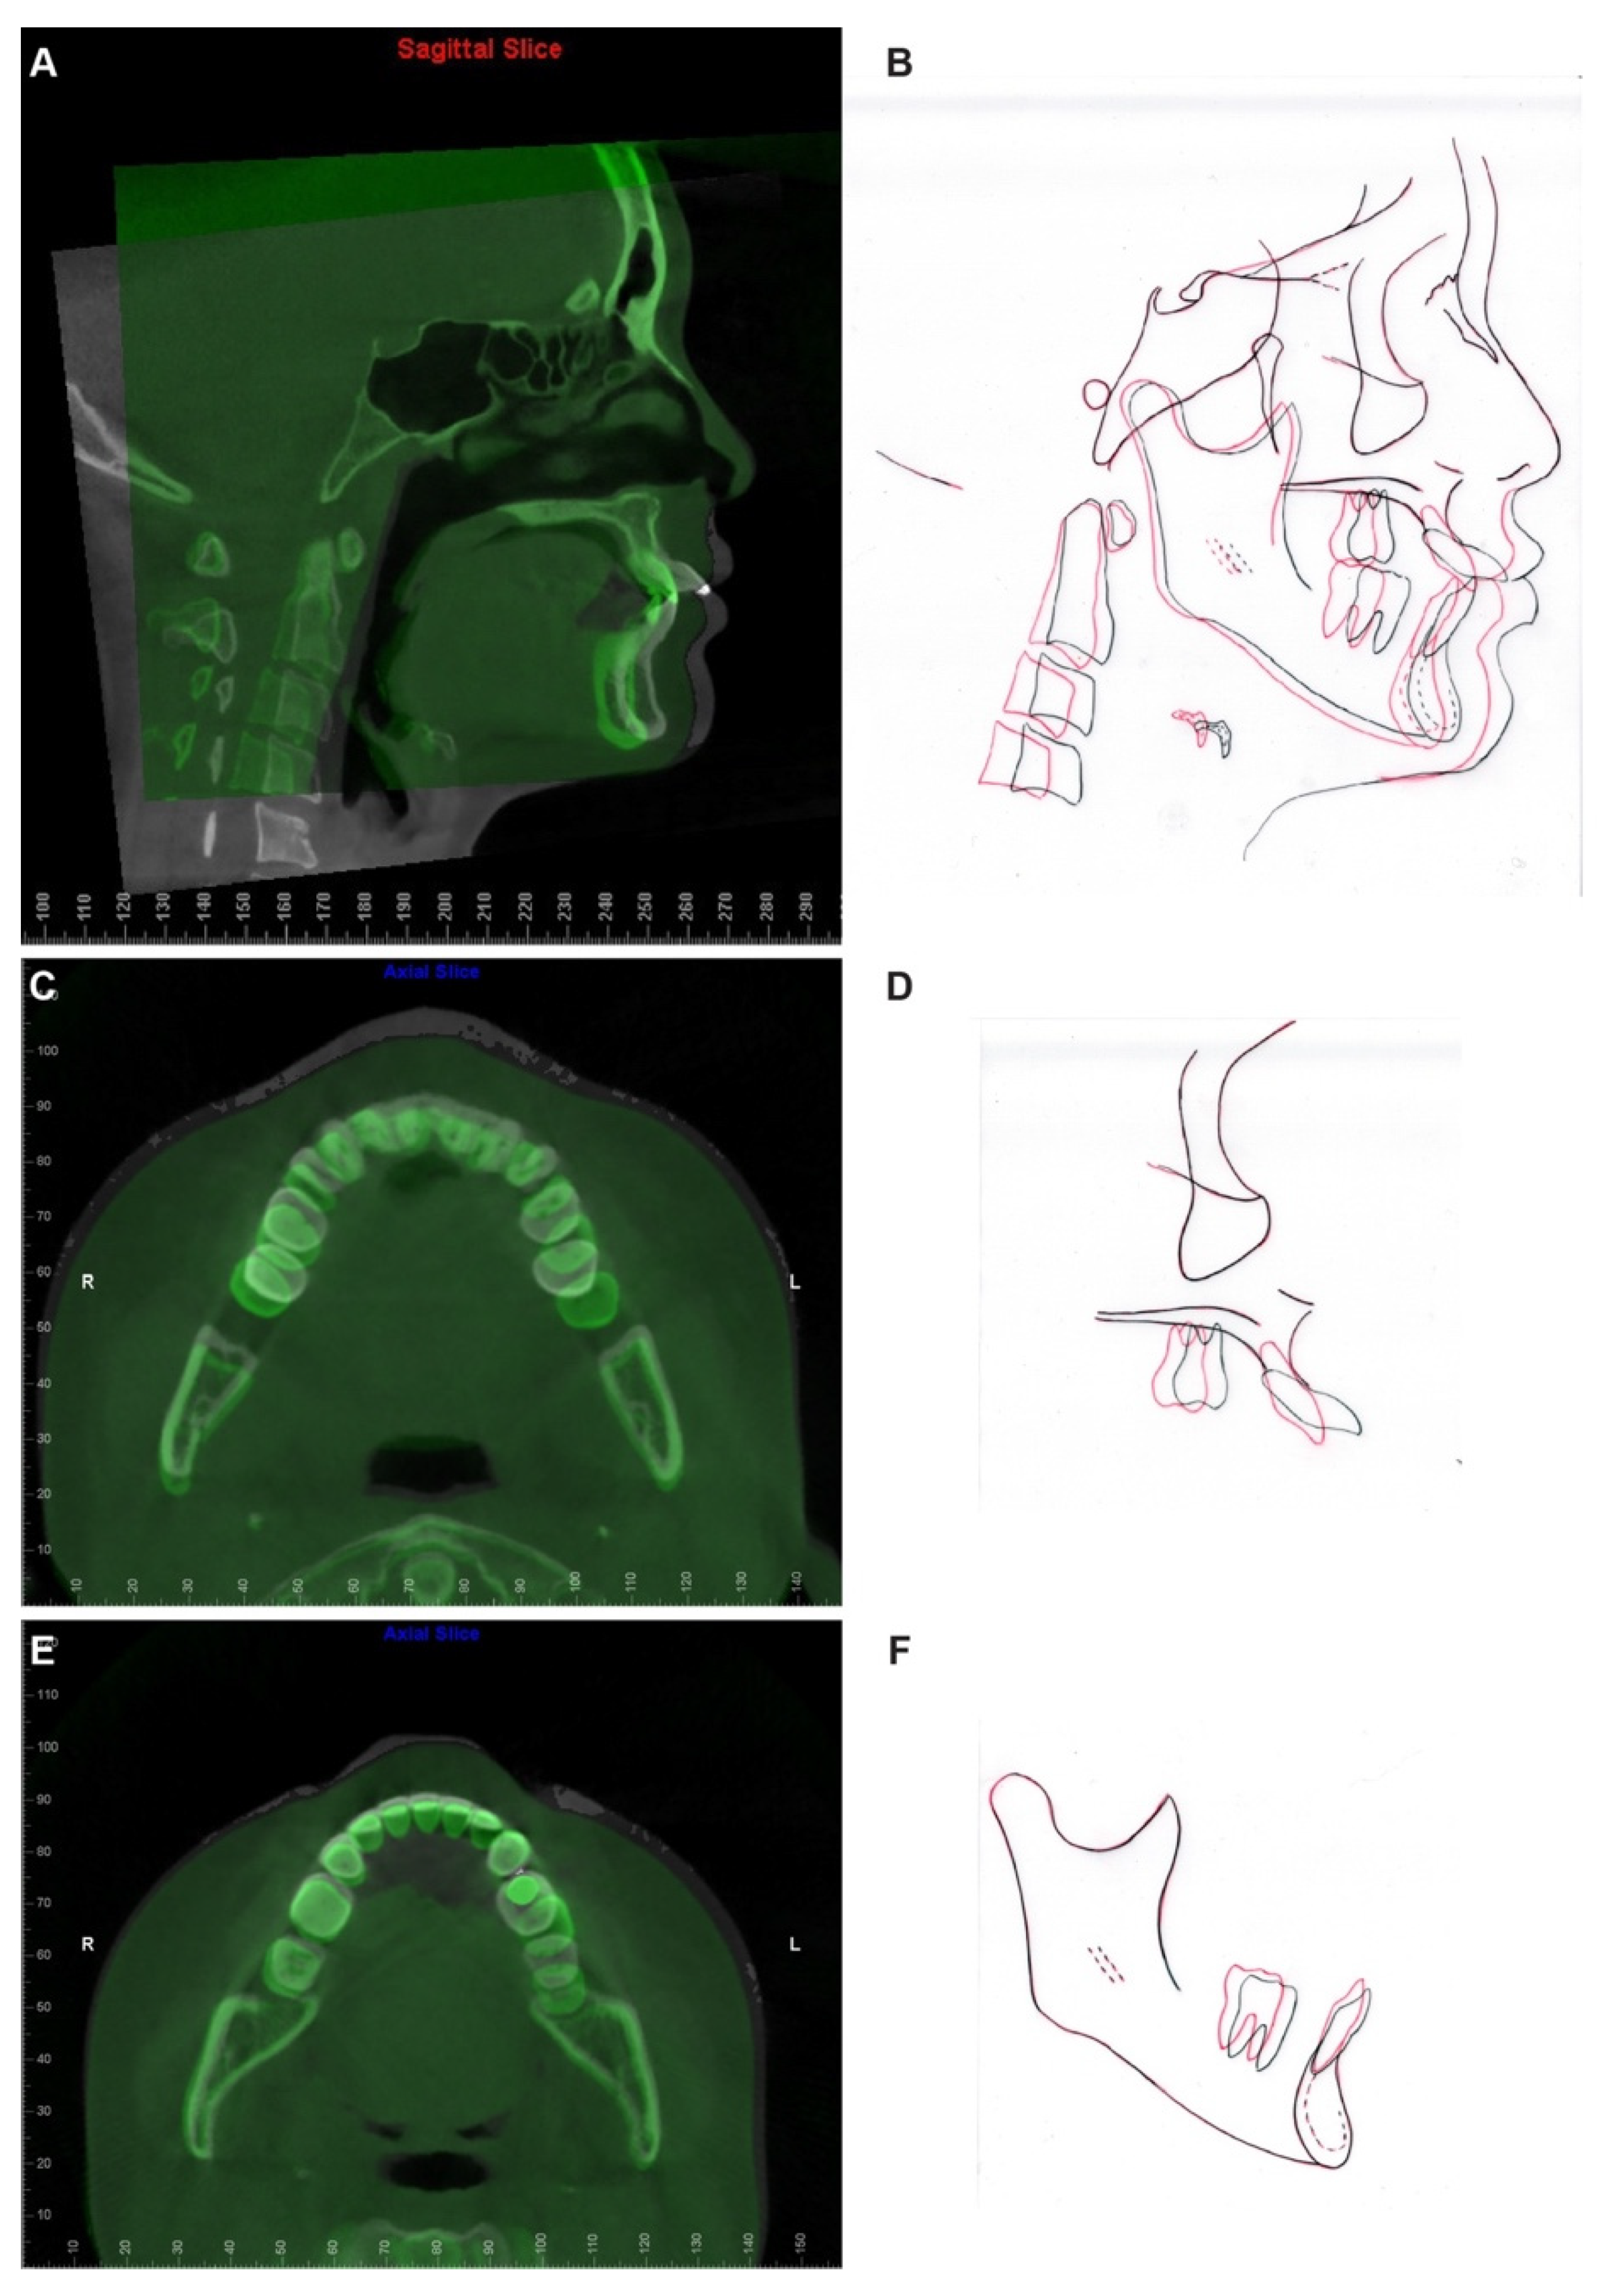

Pre- and post-treatment superimposition (Figure 12, Table 1) demonstrated the maxillary and mandibular molar distalization and anterior teeth retraction and retroclination. In detail, the maxillary central incisors were retracted 7.9 mm and retroclined 33 degrees (Figure 12A,B), the maxillary left molars were distalized 8 mm, the maxillary right molars were distalized 4 mm (Figure 12C), the mandibular left molars were distalized 5 mm, and the mandibular right molars were distalized 2 mm (Figure 12E). It is worthy to note that the molar distalization in this case has reached its anatomic limitation, as in the post-treatment panoramic X-ray (Figure 10), a limited amount of maxillary tuberosity was left distal to the maxillary left second molar, and the mandibular left second molar was position close to the retromolar fossa.

Figure 12. CBCT and cephalometric superimposition. (A) The sagittal slice at the maxillary left central incisor level of pre- (white) and post- (green) treatment CBCT images superimposed based on cranial base. (B) The superimposition of pre- (black) and post- (red) treatment cephalometric tracings superimposed based on cranial base. (C) The Axial slice of pre- (white) and post- (green) treatment CBCT images superimposed based on the cranial base. The slice was captured at the level of the cervical region of maxillary anterior teeth to demonstrate the amount of maxillary molar distalization achieved during treatment. (D) The superimposition of pre- (black) and post- (red) treatment cephalometric tracings of the maxilla. (E) The Axial slice of pre- (white) and post- (green) treatment CBCT images superimposed based on mandibular symphysis. The slice was captured at the level of the cervical region of mandibular anterior teeth to demonstrate the amount of mandibular molar distalization achieved during treatment. (F) The superimposition of pre- (black) and post- (red) treatment cephalometric tracings of the mandible.